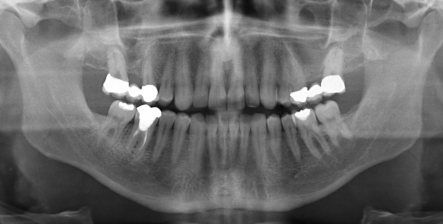

Digitales Röntgen

Aufgrund einer wesentlich geringeren Strahlenbelastung für unsere Patienten setzen wir ausschließlich digitales Röntgen ein.

Röntgenbild Durch digitales Röntgen entstandene Bilder sind detailreiche Aufnahmen, die durch ihre einfache Vergrößerungsmöglichkeiten besonders im Vorfeld von kieferchirurgischen Eingriffen Vorteile bietet.

Zudem werden keine Filme oder umweltbelastende Entwicklerchemikalien benötigt und die Röntgenbilder können auf einfache Weise archiviert werden. Digitales Röntgen ermöglicht bei Bedarf einen einfachen Datenaustausch mit Kollegen.

Obwohl die Krankenkassen bisher nur konventionelle Röntgenaufnahmen bezahlen, verlangen wir bei gesetzlich Versicherten keine Zuzahlung hierfür.